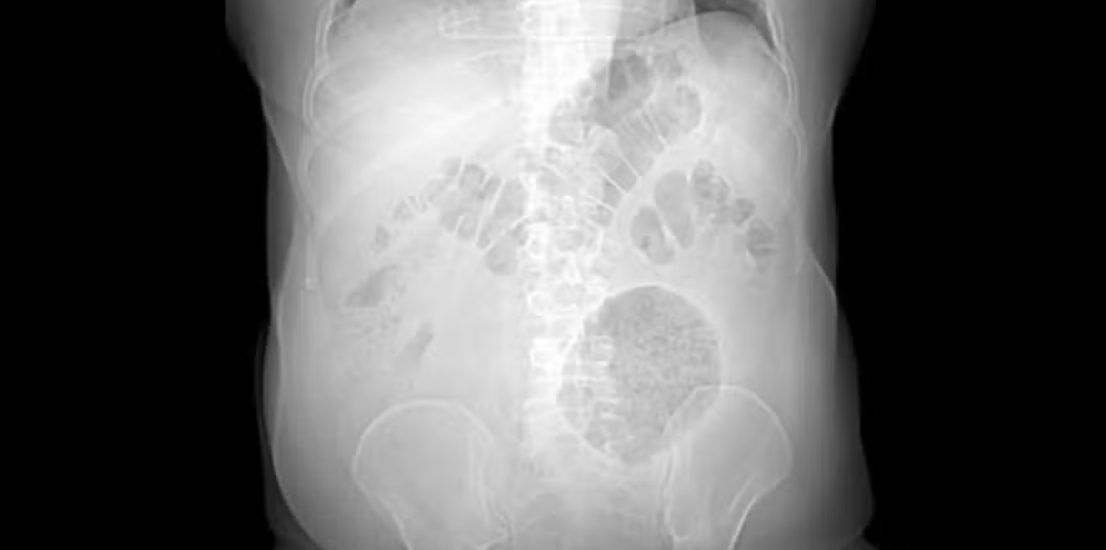

No caso atendido na capital fluminense, o homem buscou a emergência do hospital com um histórico de dores no abdômen e de perda de peso, sintomas comuns de divertículo, há pelo menos dois meses. Os médicos identificaram a presença de uma massa flácida e dolorosa no lado esquerda do abdômen, e a tomografia computadorizada confirmou o quadro.

A formação encontrada tinha 13 x 12 x 10 cm, maior até mesmo do que o máximo esperado para um caso de divertículo gigante. Os médicos realizaram, então, uma laparotomia – procedimento de abertura cirúrgica da cavidade abdominal – e confirmaram a existência da massa inflamatória na parede da porção final do intestino grosso.